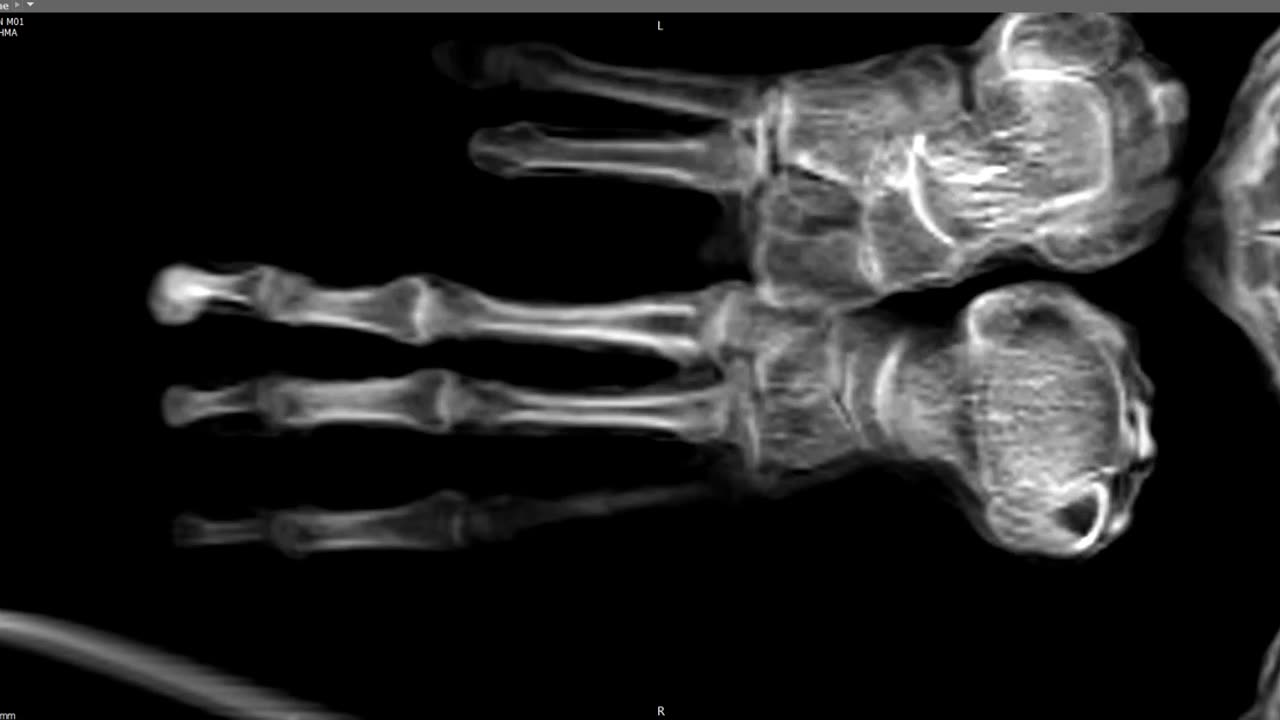

🩺👽 Maria's Tridactyl Features Confirmed Authentic | TheTruthAbove

Maria's medical scan reveals her tridactyl features are genuine and free from any manipulation, contrary to skeptics' claims. Is this the evidence we've been waiting for? 🤯 Share your thoughts in the comments below! 👉 For more compelling evidence and to uncover the truth, make sure you Like & Subscribe! #AlienBodies #MedicalEvidence #TheTruthIsOutThere